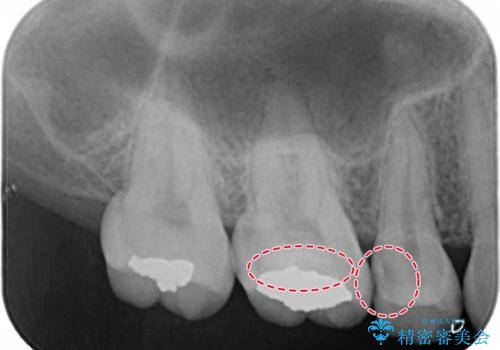

検査の結果、明らかに虫歯がある歯と修復物との間に虫歯がある歯が確認されました。

まだ虫歯が大きくなる前に処置をすることができたため神経の治療をせずに済みました。

歯と歯の間・適合の悪い修復物とその歯の間は虫歯ができることが多い場所になります。

修復物と歯の間の虫歯は、丁寧な虫歯除去と精密な修復物を装着することで予防することができます。